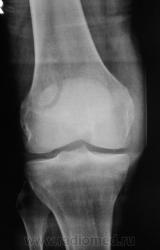

перелом надколенника( редко такой встречается) препателярная гемабурса, гемартроз, сильно пострадала суставная поверхность надколенника

Наверно все таки пателля бипартита. Представить, чтобы так красиво и ровно откололось - трудно... А мягкотканный компонент знатный...

Сам думал о "бипарцита", кстати, недавно был случай с "трипарцита". Но в данном случае был в растерянности, клиника "зашкаливает", конечно, возможно из-за мягкотканного компонента.

в литературе пишеться что пателя бипартита, чаще двустороняя и бессимптомная.. А что в анамнезе?

В минус травме говорит такая "красивенькая форма" отломка? НО при бипарите про мягкотканный компонент я данных ненашел..